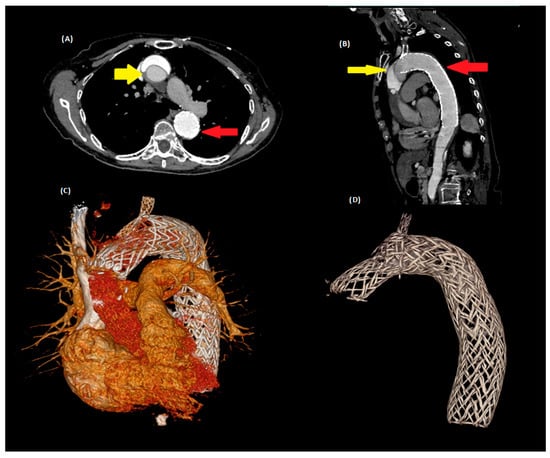

First Reported Use of the AMDS Hybrid Prosthesis for Secondary Type A Aortic Dissection After Prior TEVAR

Type A aortic dissection represents one of the most life-threatening cardiovascular emergencies, with management strategies evolving toward hybrid and endovascular approaches, particularly in high-risk patients. The Ascyrus Medical Dissection Stent (AMDS) is an emerging adjunctive technology designed to promote true lumen expansion and facilitate favorable aortic remodeling during open repair of acute Type A dissection. We present the first reported case of AMDS deployment in secondary Type A dissection following prior thoracic endovascular aortic repair (TEVAR). An 83-year-old female with extensive aortic history—including TEVAR in 2012 for intramural hematoma with chimney stenting to the left subclavian artery and carotid–subclavian bypass in 2013—developed acute Type A dissection extending into the existing stent graft in 2024. Emergency surgical intervention included ascending aortic replacement, aortic arch repair with AMDS implantation, aortic valve resuspension, and left atrial appendage resection under cardiopulmonary bypass and hypothermic circulatory arrest. Postoperative imaging confirmed appropriate AMDS positioning, false lumen exclusion, and preservation of prior endograft integrity. The patient tolerated the procedure well and was discharged in stable condition with favorable early follow-up outcomes. This case demonstrates the potential role of hybrid surgical strategies and adjunctive endovascular devices in managing complex, multi-stage aortic disease. Full article

Figure 1